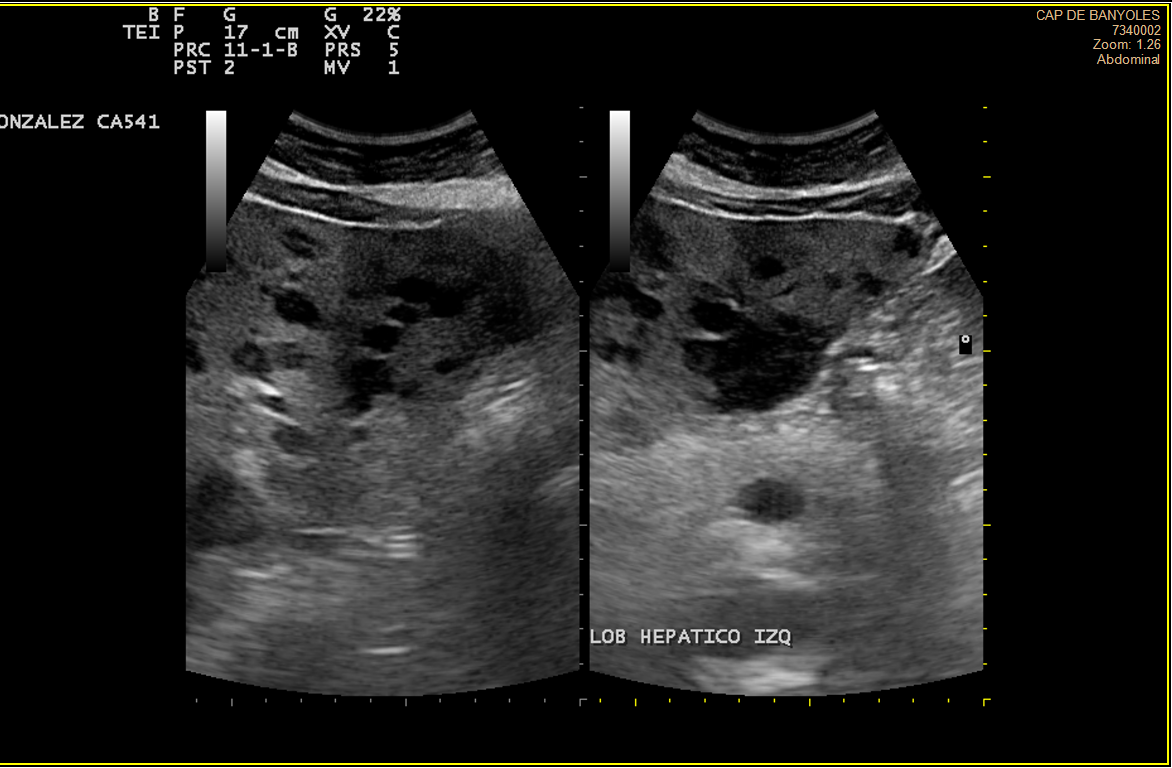

Alteración difusa de la ecoestructura hepática, presentando múltiples imágenes hipoecoicas, de diversos tamaños, resaltando una lesión en lóbulo hepático derecho de 3cm, tabicada y con ecos en su interior, con componente vascular asociado. Vesícula de aspecto normal.